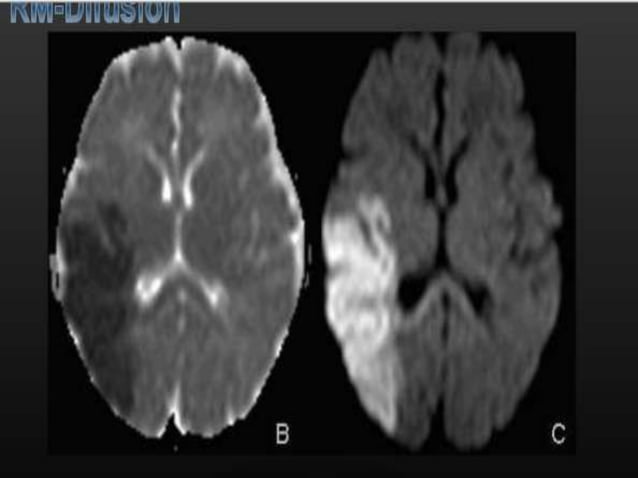

La tractografía se lleva a cabo utilizando una técnica de RM conocida como "Imagen Ponderada por Difusión", que es sensible a la difusión del agua en el cuerpo de forma que se puede utilizar para mostrar su imagen tridimensonal. La difusión libre del agua tiene lugar en estas condiciones en todas las direcciones posibles. A esto se le llama difusión "isótropa". Si el agua difunde en un medio con barreras, la difusión deja de ser uniforme, pasando a ser "anisótropa". En tal caso, la movilidad relativa de las moléculas a partir del origen tendrá una forma distinta de la esfera. En ocasiones, esta forma se modeliza como un elipsoide, y a esta técnica se la denomina imagen con tensores de difusión.

Se espera que la difusión anisótropa se incremente en áreas axonales maduras altamente ordenadas. En las afecciones en las que se distorsiona la mielina o la estructura de los axones, como en traumatismos físicos, tumores e inflamaciones reducen la isotropía, ya que las barreras a la difusión quedan afectadas por destrucción o desorganización.

La anisotropía se puede medir de múltiples formas: Una de ellas mediante una proporción llamada "anisotropía fraccional" (FA). Una anisotropía de "0" corresponde con una esfera perfecta, mientras que 1 sería una difusión lineal ideal. Los tractos bien definidos tienen una FA mayor que 0,2. Hay pocas regiones con una FA mayor de 0,9. La cifra nos proporciona información de la esfericidad de la difusión, pero no aporta nada sobre su dirección. Cada anisotropía está vinculada a una orientación del eje predominante (dirección predominante de la difusión). Los programas post-procesamiento son capaces de extraer esta información direccional.